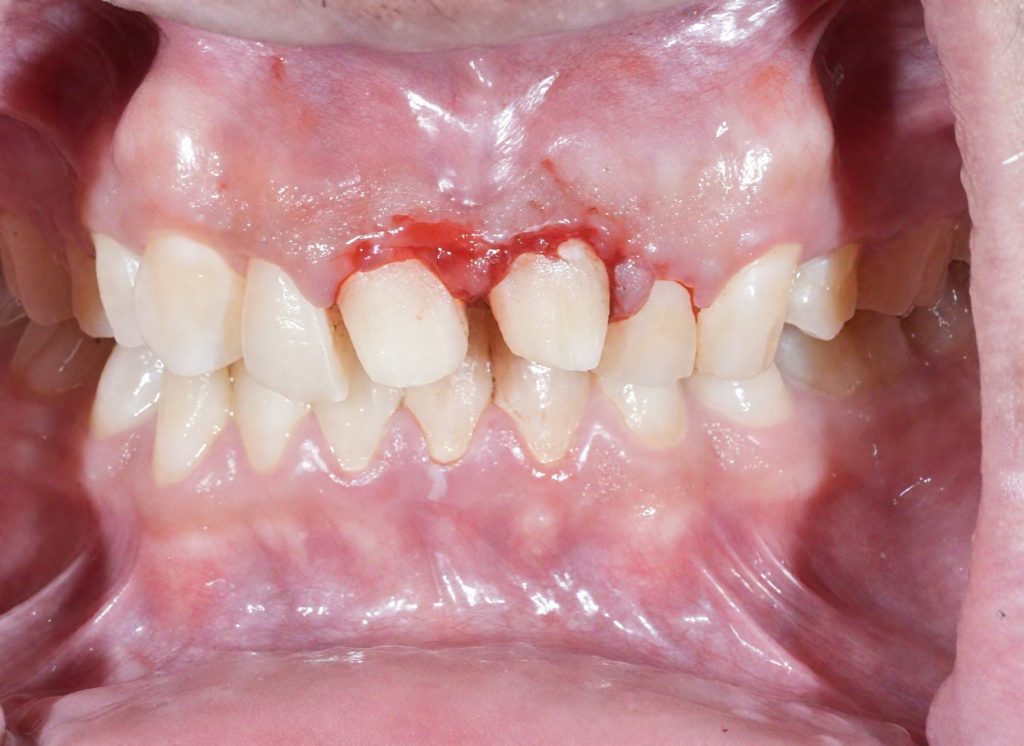

Step 3 — Conservative Emax Crown Preparation

All preparations were done under complete isolation.

- 1.0–1.2 mm labial reduction

- 1.5–2.0 mm incisal reduction

- Uniform chamfer finishing line

- Smooth internal contours

- Enamel preservation wherever possible

- Harmonized gingival zeniths

This ensured adequate thickness for lithium disilicate strength while preserving maximum tissue.